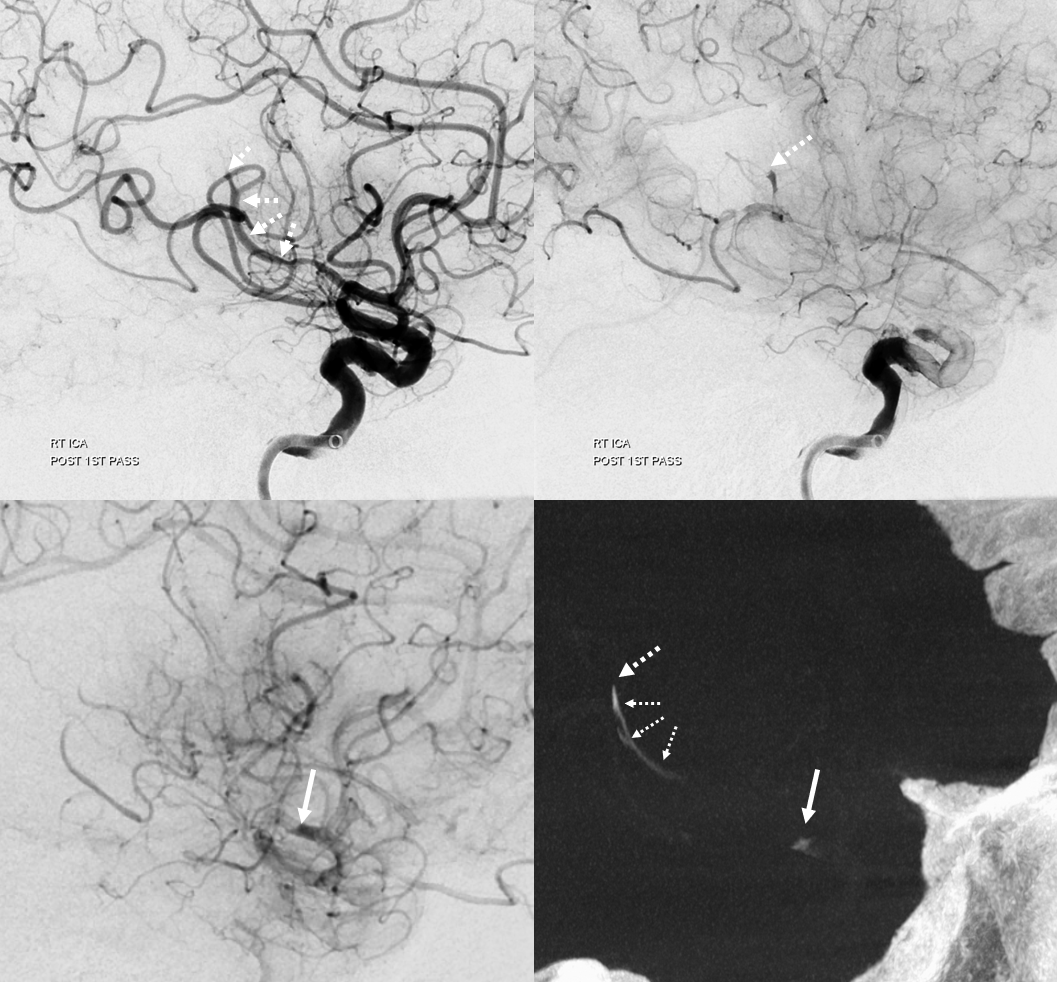

Now lets make a 3-5 mm thick MIP to see it better. We are looking at two occlusions. Each occlusion is at the distal end of the associated hyperdensity — where the contrast column stops (arrow – M2, dashed arrow — distal M2). Retrospectively one can see the distal occlusion on CTA, but not on catheter angio. Here we can definitively say that this is a tandem lesion, not a distal embolus after the upcoming proximal M2 aspiration.

As predicted there is a second occlusion. See correlation between angios and DYNA

Post. There is still one branch from this area (dashed arrow) missing plus another one in the inferior division